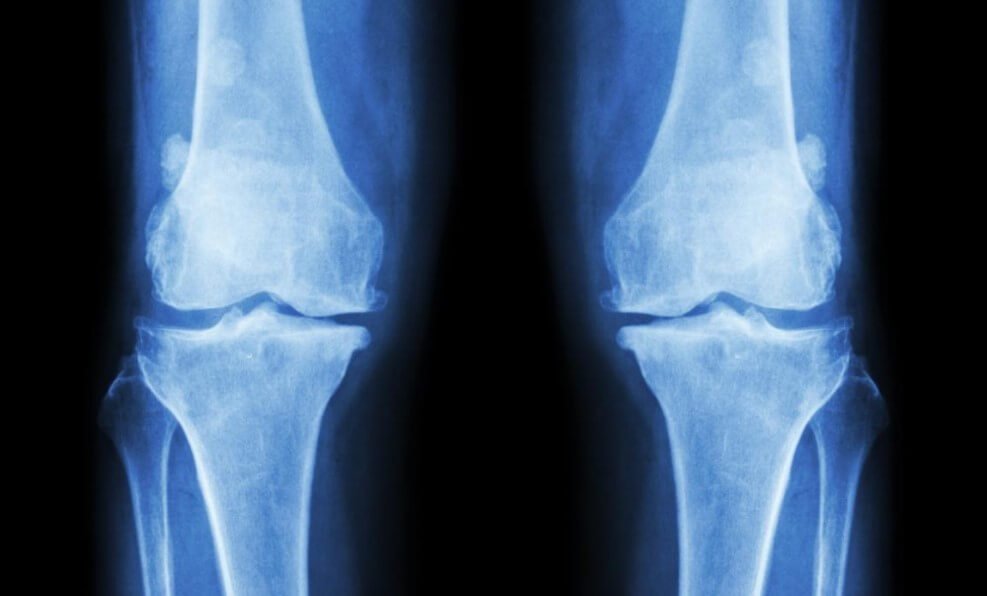

Почему у вегетарианцев хрупкие кости?

Исследование показало, что вегетарианцы и веганы чаще остальных ломают свои кости. ?? Ученые уверены, что это происходит из-за нехватки питательных веществ, которые люди обычно получают при поедании мяса. Но не все потеряно — восполнить недостаток веществ можно и сохранив привычную диету.